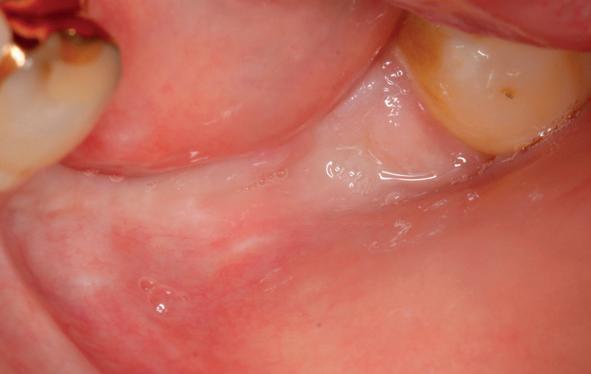

Vervaardigen essix retainer met dummies waarbij er een emergence profile van de 11 en 21 werd gevormd door eivormige dummies 4 mm in de gingiva te plaatsen

• Aanvulling zachte weefsels met de VISTA techniek en een vrij gingivatransplantaat uit het palatum links en direct dragen van de essix retainer

tinaal geslepen te worden als er geen 1,5 mm ruimte voor de vleugels behaald kan worden. De ruimte was op de dunste plekken 1 mm, dus een kleine preparatie in de 12 en 22 palatinaal was nodig. Omdat de kaak volledig afgevlakt was en dun was geworden, kunnen de dummies van de etsbrug enkel op de kaak “gelegd worden”, maar daarbij zijn er geen papillen en staat de cervicale rand van de dummies net voor de kaak. Een esthetisch resultaat kan daarmee niet behaald worden. Daarom is een aanvulling van de zachte weefsels in de breedte nodig, als het creëren van een emergence profile, waarbij het oogst alsof de gebitselementen uit het weefsel vertrekken.

Voor de aanvulling zachte weefsels chirurgie werd gekozen voor de VISTA techniek, hierbij worden er twee incisies partial thickness flap hoog in de mucosa gemaakt, waarna er ruimte vanuit de incisies wordt getunneld tussen de gingiva en het periost door middel van VISTA tunnel instrumenten. Uit het palatum links werd een vrij gingivatransplantaat geoogst van 15x10 mm met een dikte van 3 mm, die voor inhechten werd geëpithelialiseerd. Als het epitheel niet wordt verwijderd, kan deze graft door

5. Beginsituatie voor behandeling